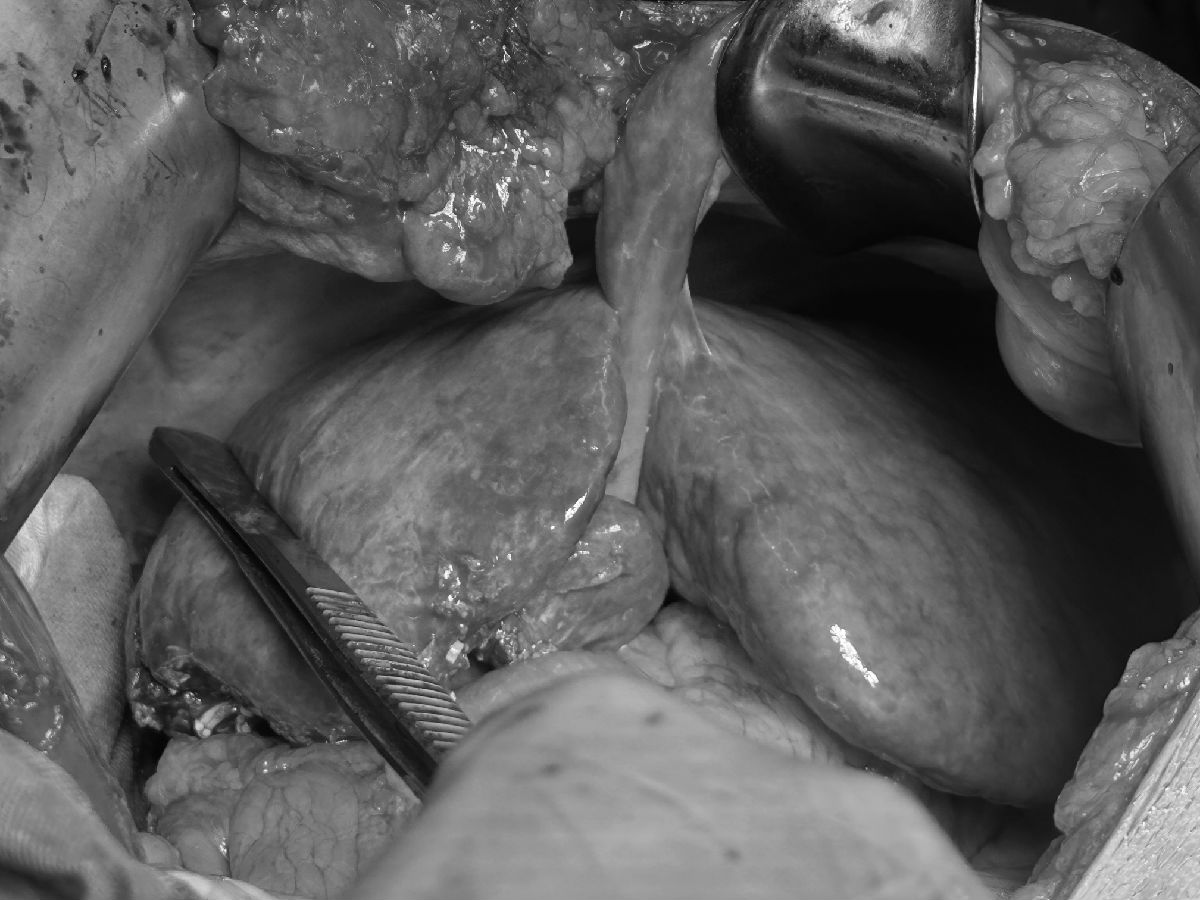

第一步,先行腹腔镜下门静脉右支结扎+左右半肝肝实质分隔(如图1),术后1月患者FLR高达69.6%(如图2)。第二步,行根治性右半肝切除术(如图3)。

图1:“养肝”技术图:左边为腹腔镜门静脉右支结扎和右肝动脉悬吊,右边为肝脏分隔后左右半肝的手术创面。

图3:根治性肝切除术后情况,剩余左半肝明显增大。